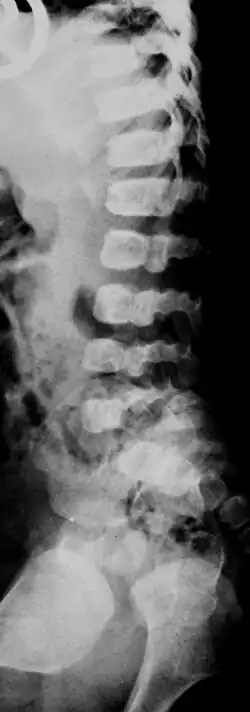

Ein Spaltwirbel (englisch cleft vertebrae; vertebral cleft, altgriechisch Spondyloschisis) ist eine angeborene Fehlbildung der Wirbelsäule. Im Gegensatz zu den Bogenschlussanomalien handelt es sich um eine Störung der Entwicklung der Wirbelkörper.[1]

Sind die rechte und die linke Hälfte des Wirbels nicht miteinander verbunden, Spalt in der Sagittalebene, spricht man von einem Schmetterlingswirbel.

Seltener treten Spalten in der Frontalebene auf, dann handelt es sich um eine „Frontale Wirbelspalte“ (englisch Coronal clefts). Als Ursache sporadisch vorkommender Spaltwirbel werden intrauterine Schäden, beispielsweise durch Medikamente (Valproat, Vitamin A) oder auch Kohlenmonoxidinhalation diskutiert[4].